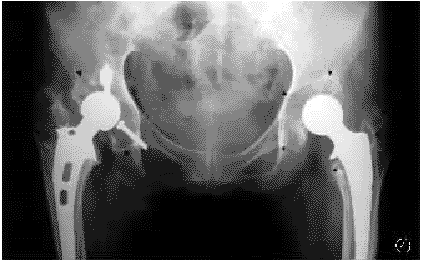

图5髋臼Delee三区及股骨近端Gruen一、二、六、七区膨胀性骨溶解(箭头所示),髋臼假体移位,股骨柄假体下沉、倾斜